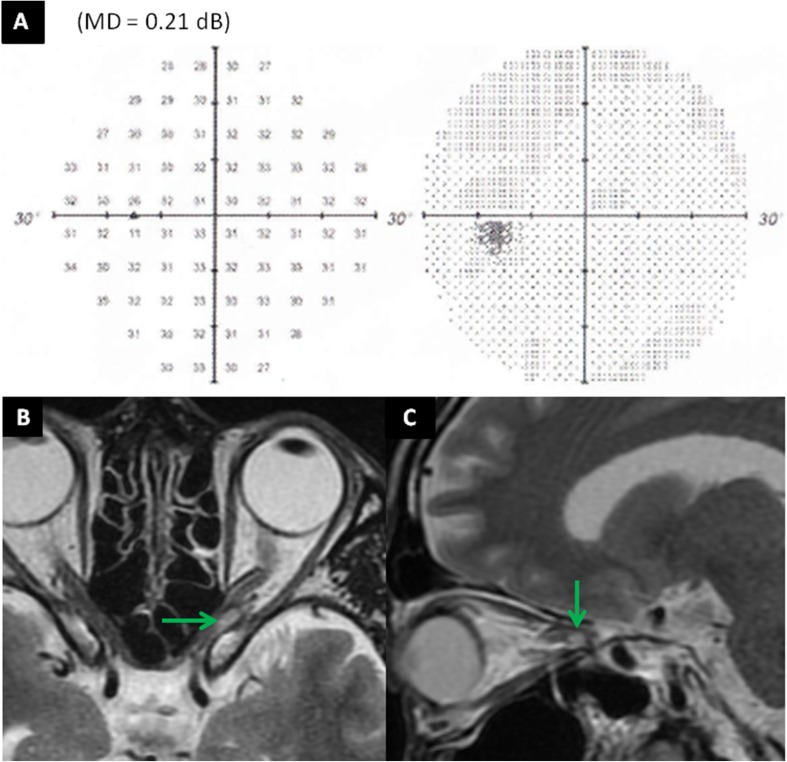

Fig. 3.

Humphrey automated perimetry showed complete disappearance of the visual field defect (a). Magnetic resonance imaging showed partial regression of the tumor (green arrow), with post-treatment dimensions of 6.5 × 3.5 × 5 mm (volume 0.1 cm3) 2.5 months after intensity-modulated radiotherapy completion (b, c)

We prospectively aimed to detect any early changes in VF occurring during the IMRT course using weekly HAP. An early change in VF was observed during the IMRT. The patient had a low-grade inferior altitudinal defect that has been detected by HAP before treatment. Repeated weekly HAP showed significant stepwise improvements in VF with a change in the mean deviation (MD) of sensitivity depression. At a dose of 46 Gy, HAP showed near-complete disappearance of the VF deficit with an MD of − 1.37 dB (p < 0.1: Fig. 1). Despite this marked improvement in VF, MRI showed little tumor reduction at a dose of 16 Gy (Fig. 2). Although HAP showed complete disappearance of the VF defect with an MD of 0.21 dB, MRI showed continued widening and winding of the ON, as well as only partial regression of the tumor with post-treatment dimensions of 6.5 × 3.5 × 5 mm (volume 0.1 cm3) 2.5 months after IMRT was completed (Fig. 3).